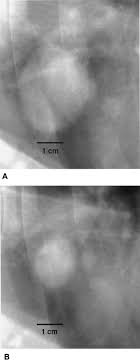

Signs Of Lung Tumor In Dogs / Image Gallery Primary Metastatic Tumors Part 1 Clinician S Brief - Sometimes a tumor can be quite. Some of the most common signs of lung cancer include: Adenocarcinoma of the lung makes up about 75 percent of all primary lung tumors in dogs. Lung cancer in pets is rare. The american veterinary medical association (avma) reports that one in four dogs will develop cancer at some time in their life and that 50% of pets over the age of 10 will develop cancer. However, there are some other symptoms that lung cancer can cause in dogs if the disease has spread to other parts of the body.

Lung Cancer In Dogs Innovet Pet from cdn.shopify.com Other clinical signs can be vague, such as: These tumors are usually benign and do not spread to other parts of the body, swanson says. Clinical signs vary with location and size of the mass, ranging from vague. Primary lung cancer is commonly carcinoma, a malignant tumor and typically attacks older dogs. Certain breeds are more predisposed to develop pulmonary tumors than others. A late complication of lung cancer in dogs can be difficulty breathing (dyspnea). However, some dogs may not present any symptoms at all. The goal is to spot the clinical signs of the condition as soon as possible to give your pet the best chance of survival.

The most common abnormal clinical sign reported in dogs with lung cancer is chronic cough. Symptoms of lung cancer (adenocarcinoma) in dogs there are many symptoms that are general in nature, such as weakness and loss of appetite, so it is sometimes difficult to know when your dog is really ill enough for a trip to the veterinarian's office. The goal is to spot the clinical signs of the condition as soon as possible to give your pet the best chance of survival. Generally, the average age of onset is between 9 and 12 years of age. The most common signs in dogs include coughing, weight loss, lethargy, and labored breathing. Pulmonary carcinomas have a high tendency to metastasize, so full. Other clinical signs can be vague, such as: These tumors are usually benign and do not spread to other parts of the body, swanson says. Specific signs will depend on where the tumor is located and may include a swollen paw, eye discharge or sores in the mouth. Melanomas in dogs tend to affect the mouth and lips, and they can also be found on their nail beds, footpads and eyes. The primary tumor might also create signs such as increased thirst, weight loss or diarrhea. In the beginning stages, many dogs show no clinical signs. Primary lung tumors (or tumors that originate in the lungs) are some of the rarest forms of cancer found in dogs.